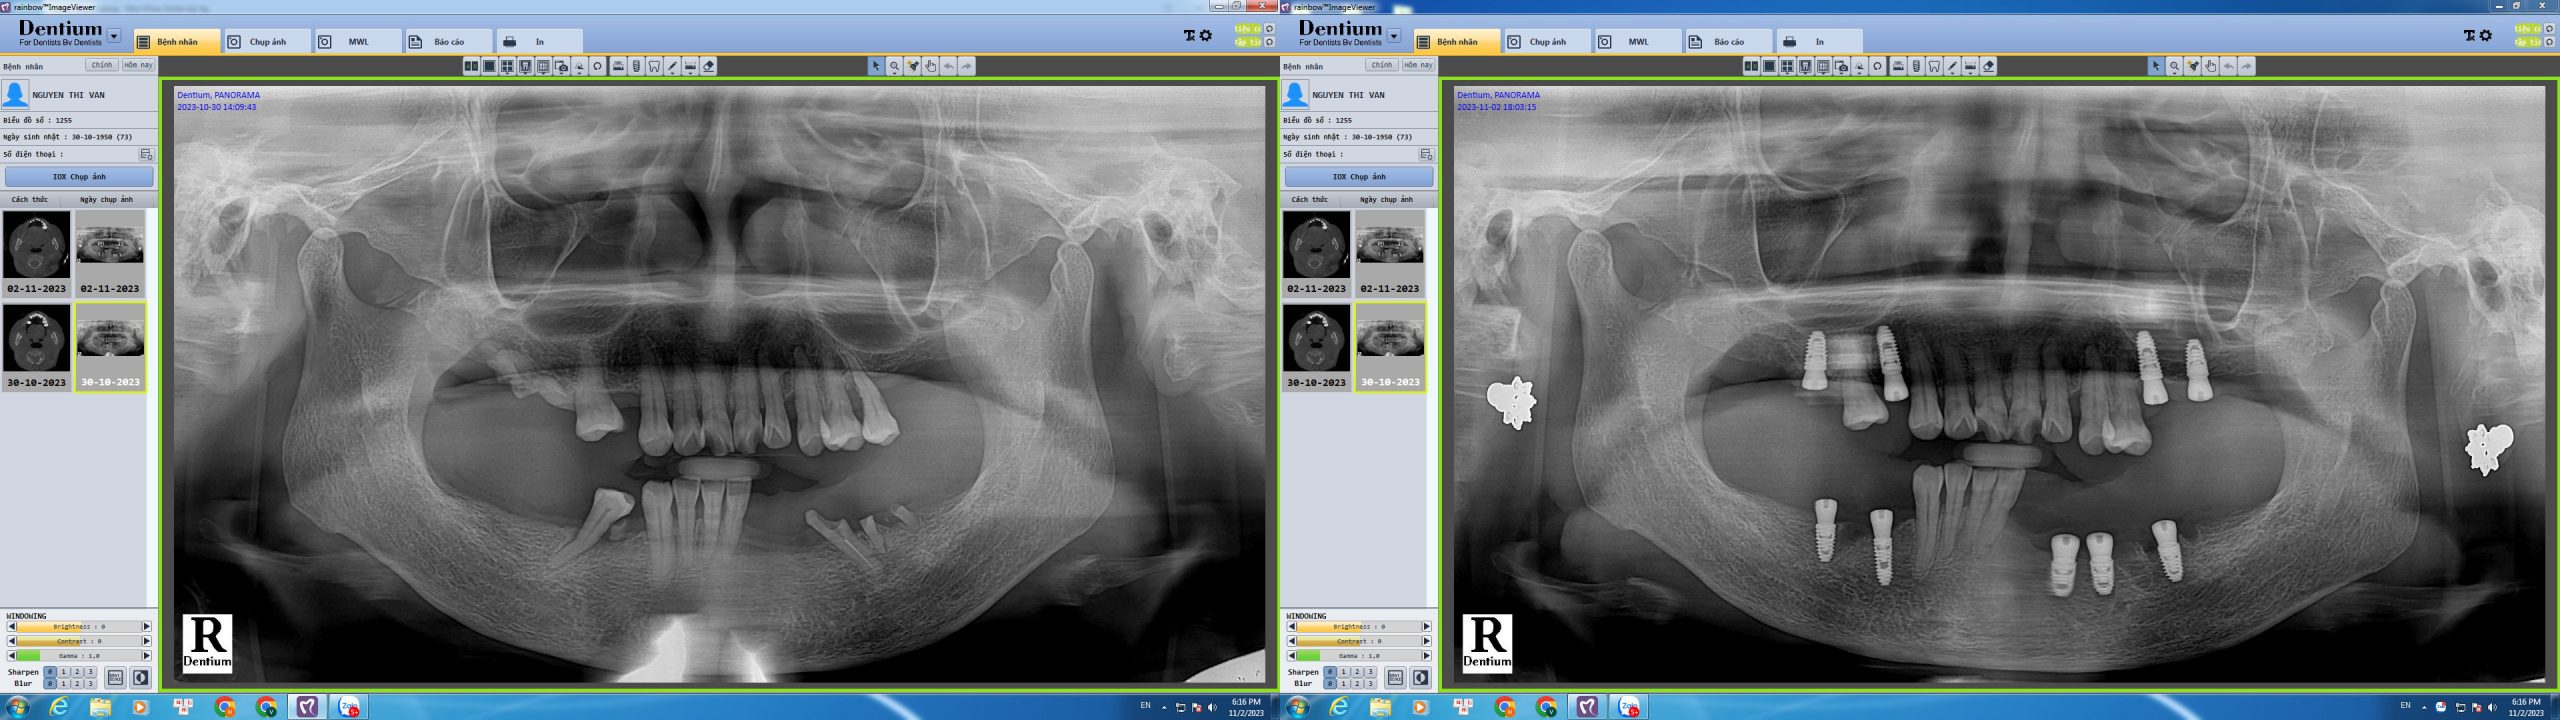

Cô Vân đã trải qua nhiều năm khó khăn trong việc ăn nhai do mất răng. Sau khi tìm hiểu kỹ lưỡng, cô quyết định chọn Nha Khoa Smile Up để thực hiện cấy ghép implant và đã có những trải nghiệm tuyệt vời. Cô Vân chia sẻ cảm xúc hạnh phúc đến mất ngủ khi có được hàm răng mới, phục hồi khả năng ăn nhai như răng thật.

Cô đã mất răng nhiều năm và gặp rất nhiều khó khăn trong sinh hoạt hàng ngày, đặc biệt là ăn uống. Sau khi tham khảo nhiều nơi, tôi quyết định chọn Nha Khoa Smile Up để thực hiện cấy ghép implant. Sự chuyên nghiệp và tận tâm của đội ngũ bác sĩ tại đây đã khiến Cô Vân yên tâm.

Quá trình cấy ghép diễn ra rất nhẹ nhàng và nhanh chóng. Cô không cảm thấy đau đớn nhiều, và các bác sĩ luôn theo dõi sát sao, đảm bảo mọi thứ diễn ra suôn sẻ. Trang thiết bị hiện đại và cơ sở vật chất khang trang tại Smile Up đã khiến Cô thực sự tin tưởng.

Sau khi hoàn thành cấy ghép, Cô Vân thực sự không thể tin vào kết quả. Hàm răng mới không chỉ giúp tôi ăn nhai tốt như răng thật mà còn cải thiện thẩm mỹ khuôn mặt rất nhiều. Cô quá hạnh phúc đến mức cả đêm không ngủ được, chỉ muốn khoe với mọi người về nụ cười mới của mình.”